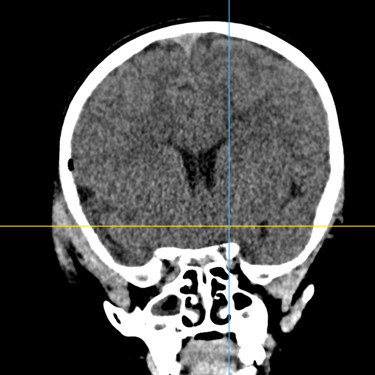

Fractura Craneal | Diagnóstico por Tomografía

La fractura craneal es una lesión que puede producirse tras un traumatismo craneoencefálico, con riesgo de comprometer el cerebro y las estructuras intracraneales. Los síntomas incluyen dolor local, edema, hematomas y, en casos graves, alteración del nivel de conciencia. La tomografía computarizada (TC) es el estudio de elección para su diagnóstico, ya que permite identificar con precisión el trazo de fractura, desplazamientos óseos, hemorragias asociadas y la afectación de senos venosos o base de cráneo. Un diagnóstico temprano mediante TC es esencial para definir la conducta terapéutica y prevenir complicaciones neurológicas potencialmente graves.